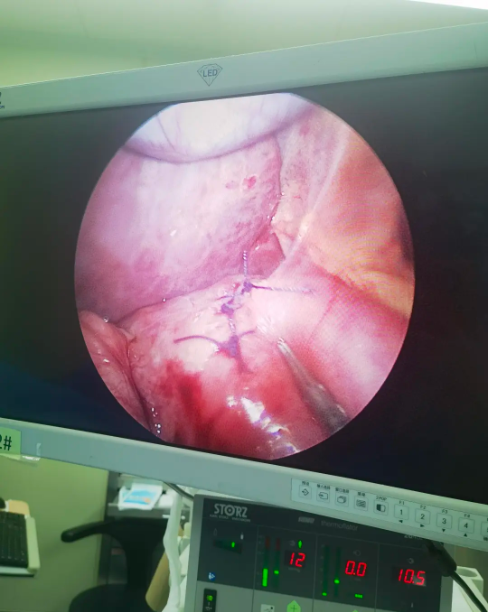

腹腔镜下,陈巍顺利完成十二指肠穿孔修补术。在儿外科主任李龙指导下,儿内科主治医师杜燕燕为患儿行急诊胃镜检查,最终确认穿孔源于十二指肠溃疡。